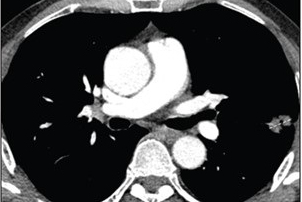

"FDG-PET has shown potential to characterize this in vivo on a macroscopic scale by capturing intratumor heterogeneity of FDG uptake and representing this spatial variation in voxel intensities," she said. "Radiomics in oncological imaging involves the extraction and interpretation of quantitative data based on the hypothesis that radiomics features may reflect underlying tumor biology. Given that FDG-PET/CT is routine in staging NSCLC, radiomics analysis of preexisting FDG-PET may improve baseline prognostication."

After a lung cancer multidisciplinary team at the Prince of Wales Hospital retrospectively reviewed 241 patients between 2012 and 2017, they selected 68 patients with histologically confirmed stage I to III NSCLC for the final study cohort. All patients had received pretreatment FDG-PET/CT within 12 weeks of beginning treatment.

Using semiautomated software (Tumour Tracker, IntelliSpace Portal Version 5, Philips Healthcare), two observers in consensus extracted 3D volumes of interest (VOI) with a minimum threshold of 2.5 standardized uptake values (SUV) from primary tumors. These VOIs were then transferred to the open-source 3D Slicer software, which was used to extract 57 first, second, and higher-order textural and shape features.